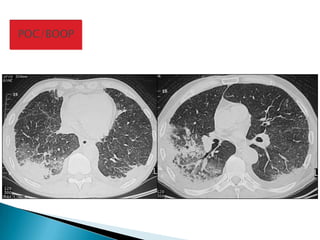

POC/BOOP

POC / BOOP: padrão nodular confluente

Arquivo do Dr. Nestor Muller

Univ. Columbia Britânica